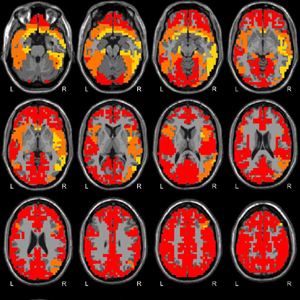

ȣȯ °¡´ÉÇÑ Á¦Ç° ¹®ÀÇÇϱâde-artifacted EEG´Â 󸮵Ǿî qEEG-Pro µ¥ÀÌÅͺ£À̽ºÀÇ °ü·Ã ¿¬·É´ë¿Í ºñ±³µË´Ï´Ù. sLORETA¸¦ »ç¿ëÇÏ¿© Linked Ears ¸ùŸÁÖ, Laplacian (CSP) ¹× ¼Ò½º À籸¼º ½ÅÈ£¿¡ ´ëÇÑ 3 °¡Áö pdf º¸°í¼°¡ ÀÛ¼ºµË´Ï´Ù. qEEG-Pro º¸°í¼´Â ´ÙÀ½°ú °°Àº ºÐ¼®À¸·Î ±¸¼ºµË´Ï´Ù.

qEEG-Pro µ¥ÀÌÅͺ£À̽º´Â 2008 ³âºÎÅÍ 2014 ³â »çÀÌ¿¡ ´º·Î Çǵå¹é (neurofeedback) Ä¡·á¸¦ ½ÃÀÛÇϱâ Àü¿¡ ÈíÀÔ ÀýÂ÷ÀÇ ÀϺηΠ°í°´À¸·ÎºÎÅÍ ±â·Ï µÈ ¸¹Àº ¼öÀÇ ÈÞ½Ä »óÅ ³úÆÄ·Î ±¸¼ºµË´Ï´Ù. qEEG-Pro µ¥ ÀÌÅͺ£À̽º´Â ´« °¨°í ´« ¶ß°í »óÅ¿¡¼ 1482 ¹× 1231 ¸íÀÇ °¢°¢ °í°´ÀÌ ÀÖ½À´Ï´Ù. ÈÞ½Ä »óÅÂÀÇ ³úÆÄ´Â ÇÏÀÌ ¿£µåÀÇ ÃֽгúÆÄ ÁõÆø±â¸¦ »ç¿ëÇÏ¿© ±â·ÏÇß½À´Ï´Ù.